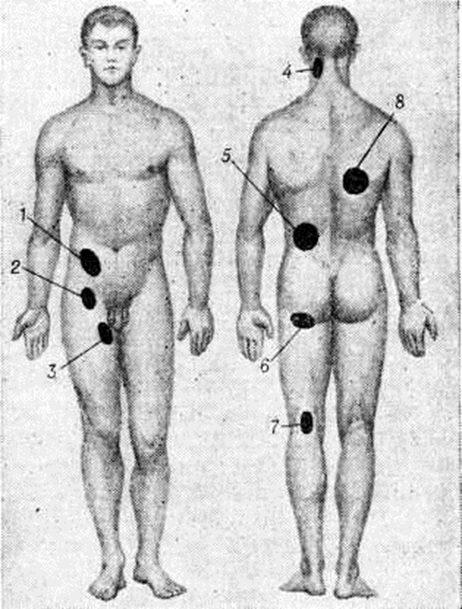

НатечникНатечник (синонимы: натечный абсцесс, холодный абсцесс, бугорчатый конгестивный абсцесс, туберкулёзный абсцесс) — скопление «холодного» (малоактивного) гноя, отграниченное соединительнотканной оболочкой, связанное со своим источником — туберкулёзным очагом в костях или суставах и имеющее склонность перемещаться по межмышечным и подапоневротическим пространствам. От Натечник следует отличать скопление «холодного» гноя вблизи очагов хронический остеомиелита, метатифозного спондилита, актиномикоза, сифилиса и другие Эти скопления — затеки (смотри полный свод знаний) образуются в результате прорыва гноя из первичного очага в окружающие мягкие ткани. В отличие от Натечник они не имеют склонности к миграции. Статистика. Натечник является характерной особенностью костно-суставного туберкулёза (смотри полный свод знаний Спондилит, Туберкулёз костей и суставов). Частота образования Натечник у больных костно-суставным туберкулёзом широко колеблется в зависимости от локализации процесса и состояния больных. По материалам П. Г. Корнева (1959), Натечник чаще всего наблюдается у больных туберкулёзом позвоночника (60%), туберкулёзным кокситом (38%), туберкулёзом локтевого сустава (25%), коленного сустава (20%) и плечевой кости (19%). Патогенез. В отличие от затёков Натечник образуется не в результате механического прорыва холодного гноя из очага в окружающие ткани. В 1837 —1839 годы Натечник И. Пирогов путём клинико-анатомических сопоставлений задолго до Ланнелонга (Одонтома М. Lannelongue, 1881) пришёл к выводу, что холодные нарывы являются следствием активного туберкулёзного процесса в мягких тканях, результатом распада в них «бугорчатого вещества». В последующем этот вывод нашёл подтверждение и развитие в трудах А. Натечник Чистовича (1936), П. Г. Корнева (1953), А. И. Струкова. По современным представлениям, Натечник представляет собой активную туберкулёзную гранулему, которая в случае недостаточности защитных механизмов организма разрастается, захватывая все новые ткани. Распространение (миграция) Натечник идёт по рыхлым соединительнотканным прослойкам, межмышечным и подапоневротическим пространствам, что обусловливает типичность локализации Натечник Натечник может возникнуть либо непосредственно близ поражённого отдела кости, либо вдали от него вследствие распространения туберкулёзного процесса по рыхлым соединительнотканным прослойкам. При поражении шейных и верхних грудных позвонков образуются подзатылочные (рисунок 1, 4) и заглоточные Натечник В грудном отделе позвоночника обычно не отмечается значительных продвижений Натечник Они остаются «сидячими» в виде «ласточкиных гнёзд» (термин предложен П. Г. Корневым в 1953 г.), а иногда выявляются паравертебрально в межлопаточной области (рисунок 1, 8). В поясничном отделе позвоночника Натечник иногда проникают кзади в поясничный треугольник (trigonum Petiti — рисунок 1, 5), в редких случаях — в толщу ягодичных мышц и даже в подколенную ямку (рисунок 1, в и 7). Наиболее часто, располагаясь внутри апоневротического влагалища большой поясничной мышцы, они выявляются в подвздошных областях и проникают через мышечную лакуну на бедро (рисунок 1, 7, 2, 3). Миграция Натечник наблюдается также и при туберкулёзном коксите вследствие наличия на бедре массивных мышечных групп. При поражении коленного сустава Натечник могут обнаруживаться на передней поверхности бедра под четырёхглавой мышцей, а при оститах проксимального конца большеберцовой кости спускаются вниз под икроножные мышцы и могут подниматься вверх: к суставу, инфицируя его извне (рисунок 2). Патологическая анатомия характерна для туберкулёзного процесса. При гисто л. исследовании находят специфические клеточные элементы по типу гранулемы с творожисто-некротическим распадом, гнойным расплавлением и образованием на её месте полости, окружённой оболочкой из туберкулёзных грануляций. Клиническая картина характеризуется общими и местными симптомами. Общая симптоматика обусловлена интоксикацией продуктами распада поражённых туберкулёзом тканей, особенно при больших скоплениях гноя, и проявляется снижением общего тонуса больного, ухудшением его состояния, потерей аппетита, падением веса, повышением температуры тела, иногда до 38,5°, нередко изменением английский показателей (анемия, ускоренная РОЭ, сдвиг лейкоцитарной формулы влево без заметного лейкоцитоза). |